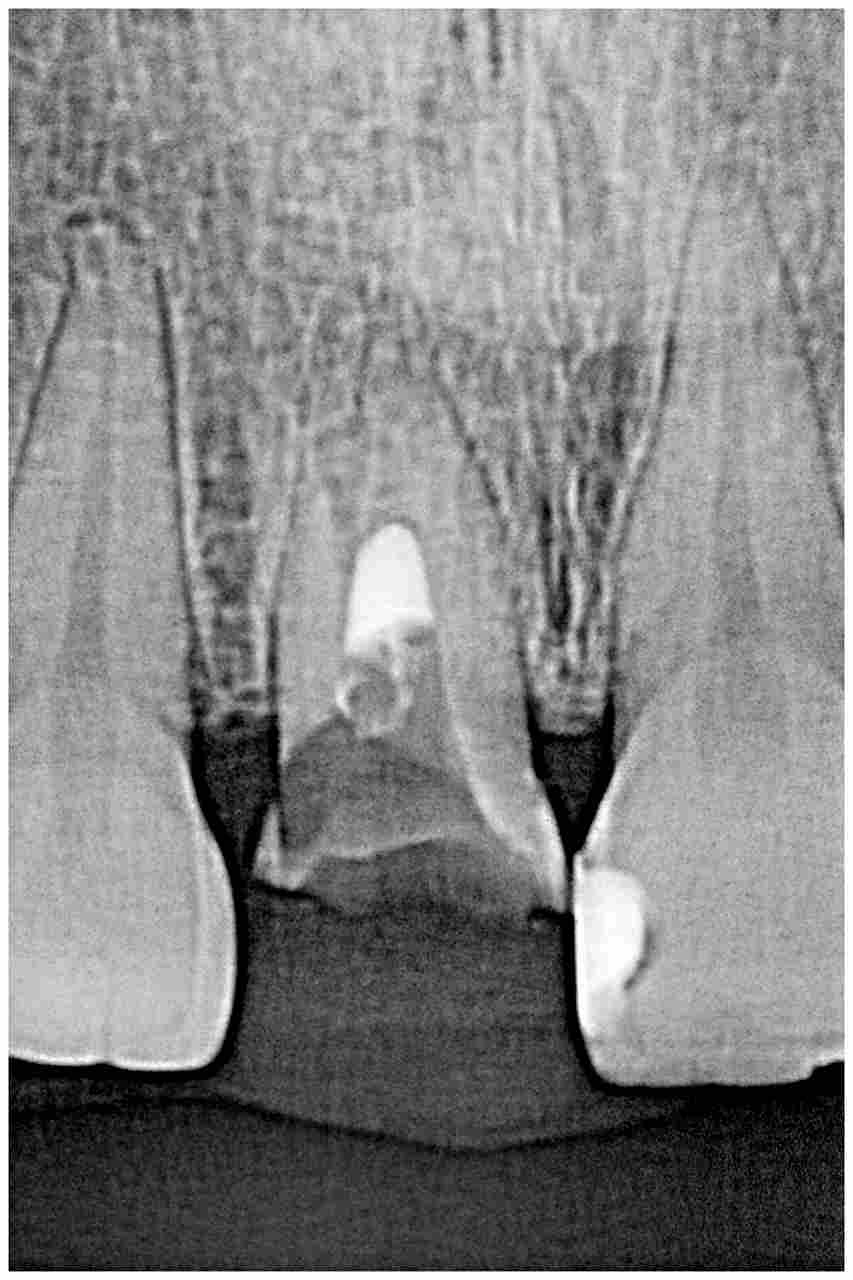

デンタルレントゲンになります

根尖も大きく開いており確かに保存不能の状態でした